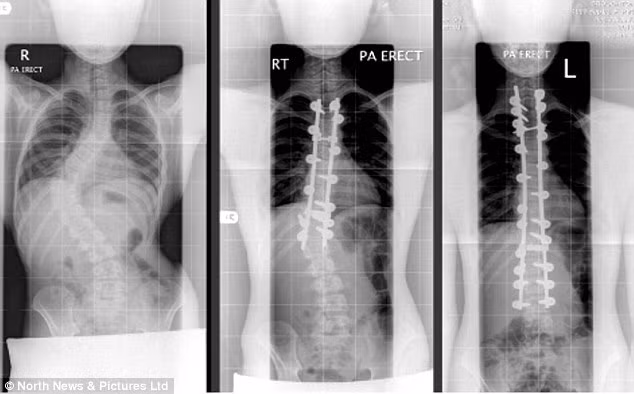

Các bác sĩ cho hay trường hợp của Amy cực kỳ nghiêm trọng bởi cột sống uốn cong thành góc 70 độ. Thậm chí các chuyên gia cũng cảnh báo cô bé có thể bị tê liệt vĩnh viễn và bị nghiền nát nội tạng do cột sống uốn cong.

Dấu hiệu đầu tiên của chứng bệnh này chỉ là một khối u mọc trên lưng. Đầu tháng 4/2006, cô mới được chẩn đoán chính xác là mắc chứng bệnh vẹo cột sống nặng - cột sống xoắn theo hình chữ S bất thường.

Sau 10 năm, trải qua nhiều phương pháp trị liệu nư chèn thanh titan cố định xương sống, mặc áo niềng xương cố định 4 năm...Amy đã có thể đứng thẳng.